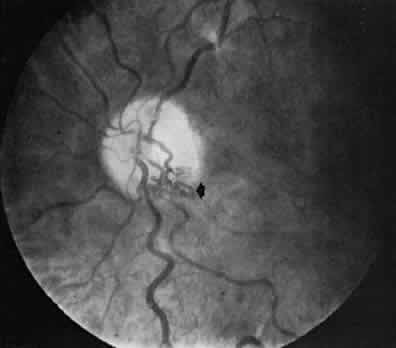

In as many as 20% of normal eyes, a cilioretinal artery may exist as well.11 These are vessels that directly connect the posterior ciliary circulation to the retinal circulation. Clinically, they can usually be identified by their ophthalmoscopic appearance. Cilioretinal vessels emerge from the edge of the optic disc, with no apparent connection to the central retinal vessels (Fig. 2). Fluorescein angiography shows them to fill with the choroidal circulation. They are usually temporally located on the optic disc but rarely can be nasal. Multiple vessels may be present. Cilioretinal arteries are the easiest to identify. The existence of cilioretinal venous channels in normal eyes is a subject of debate.12 Acquired cilioretinal veins, referred to as optociliary anastomoses or incorrectly as optociliary shunts, can develop in pathologic processes such as obstruction of the CRV or in optic nerve tumors (Fig. 3).

Fig. 2. The cilioretinal artery hooks around the temporal margin of the disc edge (*). (Henkind P, Benjamin JV: Trans Ophthalmol Soc UK 96:418, 1976)